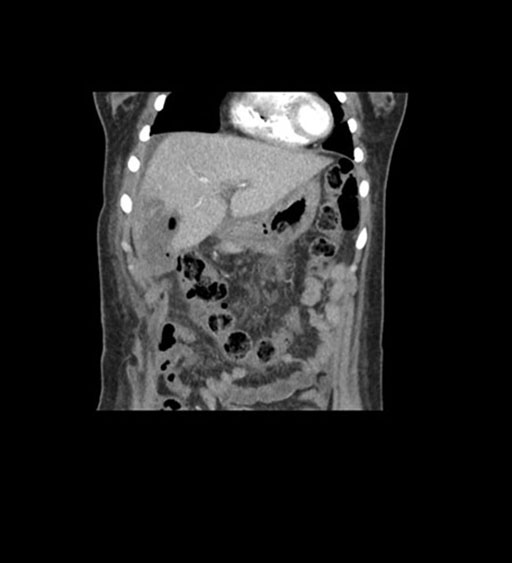

Coronal Arterial